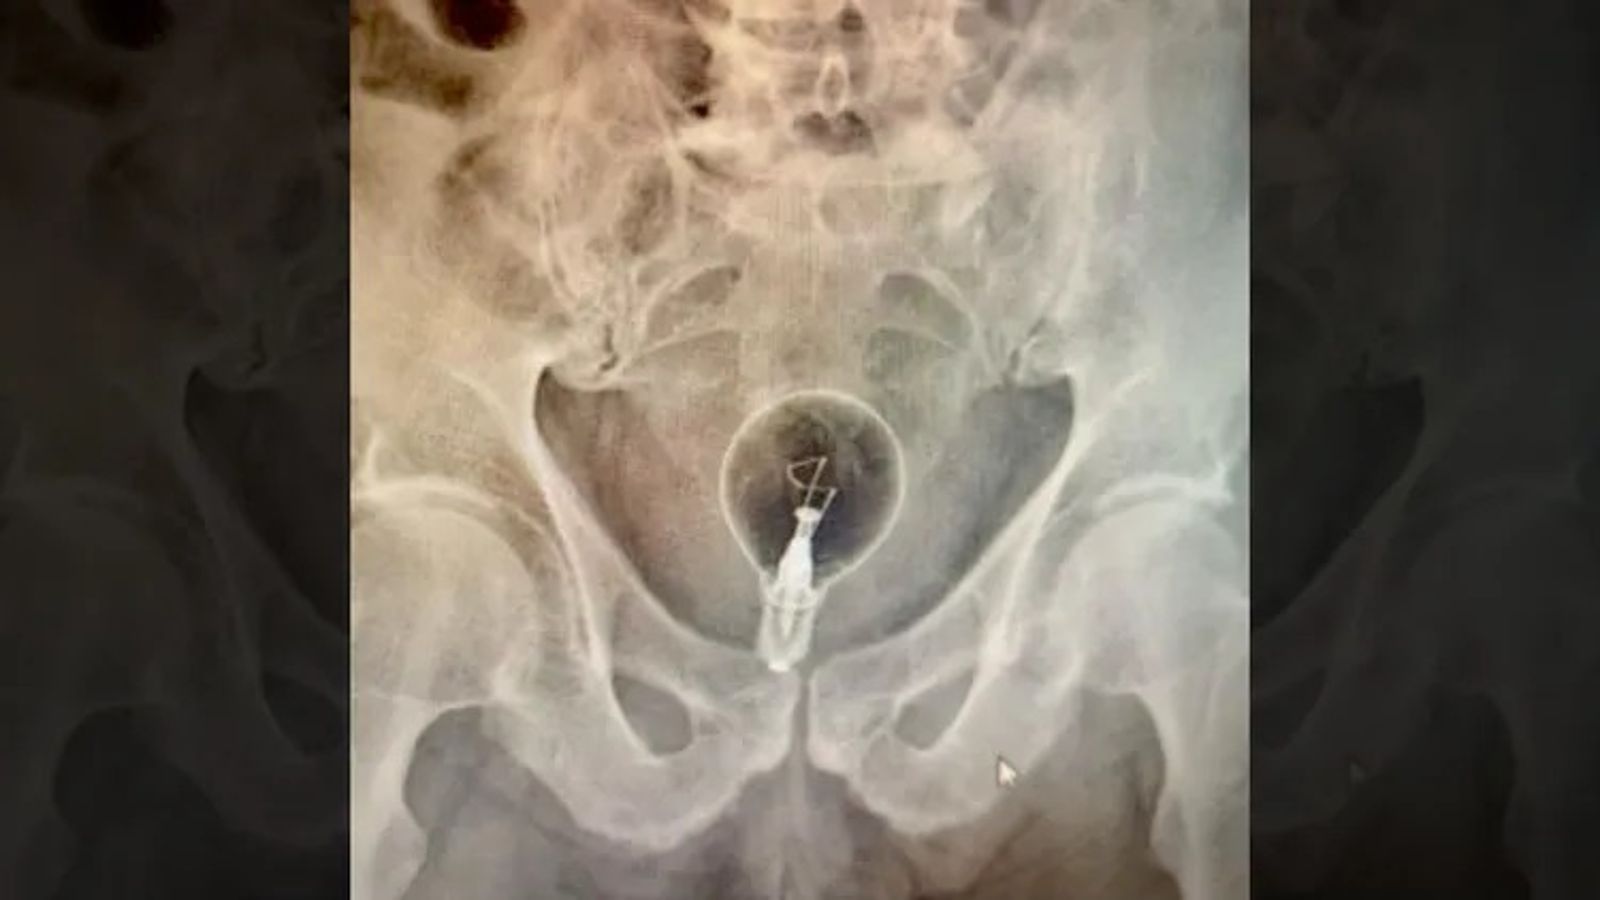

事實上,這並非第一次有人將「燈泡」塞入體內,先前哥倫比亞的腸胃病學家兼內科醫師Julian Pylori就分享一名53歲男性因肛門疼痛就醫,拍X光照後驚見他直腸裡塞著一顆大燈泡,所幸該顆電燈泡並沒有在體內破裂,也順利取出。